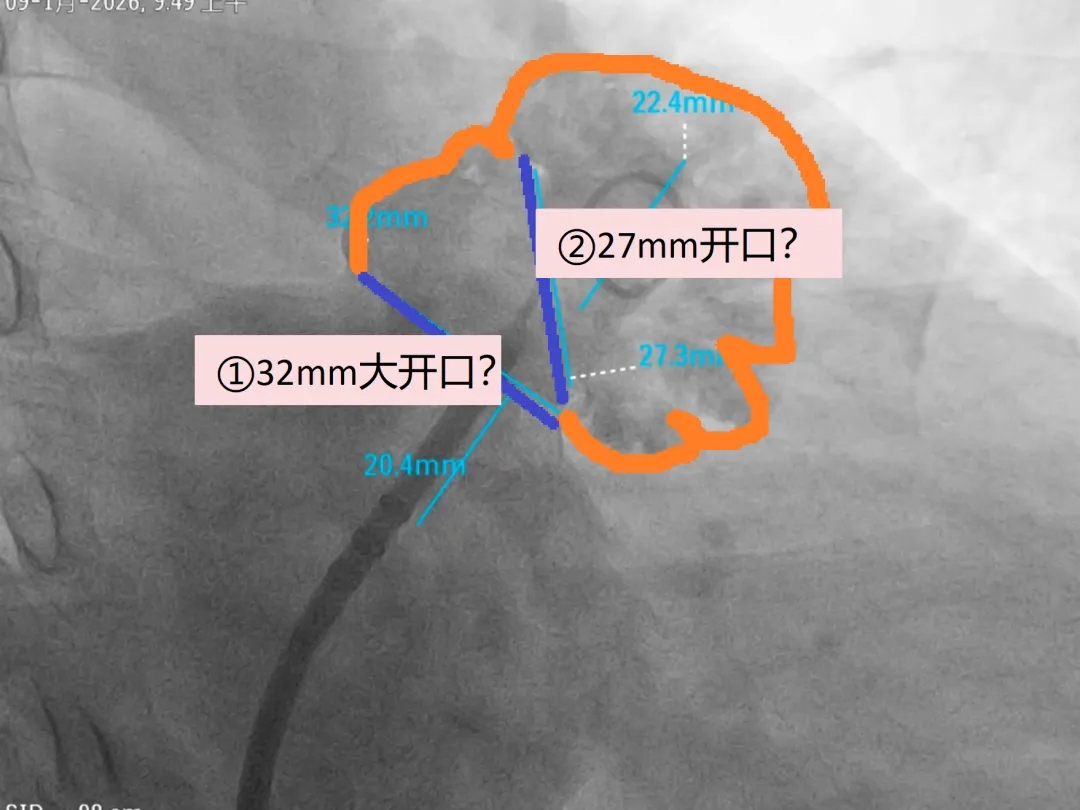

术中DSA肝位造影

心耳呈菜花状,梳状肌发达

心耳内无血栓

开口32.2mm,深度超过22.4mm

心耳的形态判断:结合肝位测量及术前TEE四个角度数据判断该心耳开口椭圆形;

心耳内梳状肌分布判断:DSA造影判断心耳内梳状肌发达;

基于MemoLefort封堵器的设计特点:自适应高回弹镍钛合金骨架可提供径向支撑和贴壁成角倒刺稳定挂靠心耳内部,最终选用LAFDQ-32封堵器,在DSA指导下保持鞘管张力将鞘管维持向上轴向进行封堵。